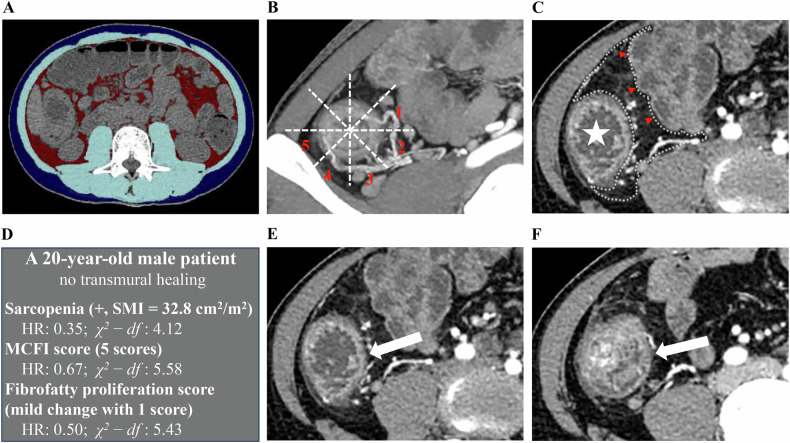

Results: This study included 113 patients, and TH occurred in 26 (23. 0%) patients. The results of the univariable analysis indicated a statistically significant association of the presence of sarcopenia, higher MCFI score, and higher fibrofatty proliferation score with an increased failure rate of TH. We found no evidence that skeletal muscle index, subcutaneous adipose index, visceral adipose index, and visceral adipose/subcutaneous adipose area ratio were associated with TH. Multivariable analysis revealed that sarcopenia (Hazard ratio (HR): 0.35, 95% CI: 0.14-0.87, p = 0.023), MCFI score (HR: 0.67, 95% CI: 0.49-0.91, p = 0.010) and fibrofatty proliferation score (HR: 0.50, 95% CI: 0.29-0.85, p = 0.011) remained significant. MCFI score (χ2-df = 5.58) was the most critical factor for TH prediction, followed by fibrofatty proliferation score (χ2-df = 5.43) and sarcopenia (χ2-df = 4.12).

目的:我们研究了基线计算机断层扫描肠图(CTE)评估的身体成分参数是否可以预测接受Ustekinumab (UST)治疗的克罗恩病(CD)患者的经壁愈合(TH)。材料和方法:纳入2020年8月至2022年8月接受标准UST治疗的成年活动性CD患者。身体组成,包括蠕动脂肪(CF、肠系膜蠕动脂肪指数(MCFI)和纤维脂肪增殖评分)、骨骼肌、内脏脂肪和皮下脂肪相关参数在基线CTE上进行评估。采用Cox回归分析确定TH的独立预测因素。结果:本研究纳入113例患者,26例(23例)发生TH。0%)患者。单变量分析结果显示,肌肉减少症的存在、较高的MCFI评分和较高的纤维脂肪增殖评分与TH失败率增加具有统计学意义。我们没有发现骨骼肌指数、皮下脂肪指数、内脏脂肪指数和内脏脂肪/皮下脂肪面积比与TH相关的证据。多变量分析显示,肌肉减少症(风险比(HR): 0.35, 95% CI: 0.14-0.87, p = 0.023)、MCFI评分(HR: 0.67, 95% CI: 0.49-0.91, p = 0.010)和纤维脂肪增殖评分(HR: 0.50, 95% CI: 0.29-0.85, p = 0.011)仍然显著。MCFI评分(χ2-df = 5.58)是预测TH的最关键因素,其次是纤维脂肪增殖评分(χ2-df = 5.43)和肌肉减少症(χ2-df = 4.12)。结论:在所有体成分参数中,基线CTE评估的MCFI和纤维脂肪增殖评分与TH独立相关,与肌少症相比,它们具有更大的预测功效。关键相关性声明:基线CTE上的脂肪增加是接受Ustekinumab治疗的克罗恩病患者经壁愈合的重要预测因素,可实现患者的早期风险分层,并对决策具有潜在影响。关键点:确定跨壁愈合的预测因素可以为早期剂量优化提供见解,以提高跨壁愈合率。较高的蠕动脂肪评分(肠系膜蠕动脂肪指数和纤维脂肪增殖)与较低的跨壁愈合率独立相关。肠系膜蠕动脂肪指数和纤维脂肪增殖评分与肌少症相比显示出更大的预测效果。